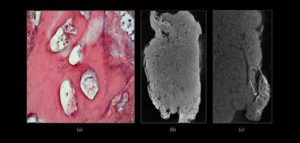

Es un tumor odontogénico benigno de origen epitelial y mesenquimal caracterizado por un crecimiento lento y de contenidos dentales (Esmalte, dentina, cemento y pulpa). Se